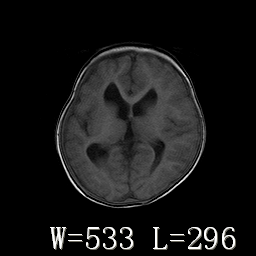

标题: PED3252:脑室增大。

女,3岁,3岁不会说话,阵发性抽搐、自伤。

考虑为梗阻性脑积水(中脑导水管狭窄)。

侧脑室不规则,前后角尖角样,脑白质较少:考虑灰质发育不良可能

倒数第3附图不是这个病人的吧!考虑脑白质发育不良可能。

右侧额叶发育不良!

右侧额叶发育不良。

右侧额叶发育不良

考虑,脑发育不良,胼胝体发育不全?(图片不全,矢状位?)